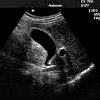

УЗИ органов брюшной полости. Комплексная диагностическая процедура, при которой визуализируются печень, желчный пузырь и его протоки, поджелудочная железа, селезенка и сосуды. Исследование позволяет выявить опухоли, воспалительные заболевания, камни, кисты, последствия травм. Выполняется в в-режиме, дополнительно производится УЗДГ судов. Вместе с УЗИ УЗИ иногда исследуют забрюшинное пространство, почки. Стоимость определяется количеством изученных органов.

УЗИ органов брюшной полости начинается с визуализации печени и правой почки. Определяются степень их эхогенности, однородность структуры ткани, сосудистый рисунок и четкость контуров. Затем оценивается анехогенность, форма и свет желчного пузыря, расположение и характеристики стенок воротной вены и основного желчного протока. Затем исследуется структура поджелудочной железы, селезенки, крупных вен и артерий.Во время исследования почек определяются их размеры, их структура, их контуры и их положение. В забрюшинном пространстве визуализируются надпочечники, забрюшинная клетчатка, лимфатические узлы и крупные сосуды. Полые органы желудочно-кишечного тракта детально не изучены, но можно обнаружить скопление жидкости в тонкой и толстой кишке. УЗИ диагностируют следующие группы патологий: